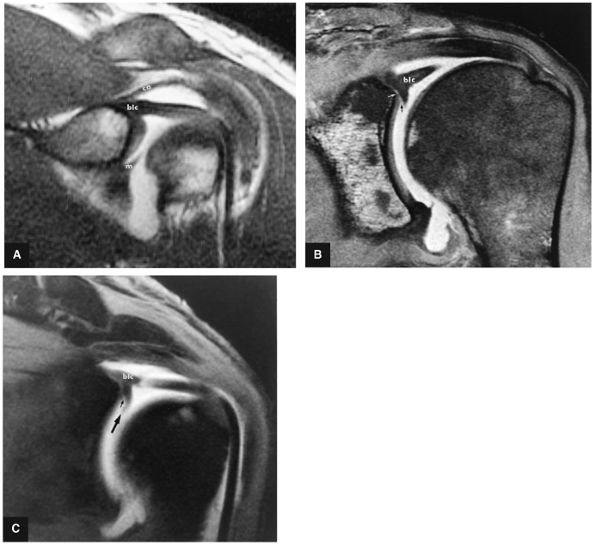

FIGURE 8.74 ● Biceps labral complex (blc) attachments. (A) In type 1, the BLC is firmly attached to the superior pole of the glenoid. m, middle glenohumeral ligament; ca, coracoacromial ligament. (B) In type 2, the biceps is attached to the superior labrum lateral to the superior glenoid. A fluid-filled sublabral sulcus (black arrow) is formed at the superior pole of the glenoid. Intermediate-signal-intensity cartilage (white arrow) of the glenoid extends medially over the superior glenoid surface. (C) Meniscoid labrum (large arrow) associated with a large sulcus (small arrow), which extends underneath the meniscoid superior labrum. FS T1-weighted coronal oblique MR arthrography images.

FIGURE 8.75 ● (A) Type 1 BLC with superior labrum firmly attached to the superior pole of the glenoid. The type 1 BLC may be seen in the posterior wedge labrum and the anterior wedge labrum. (B) Coronal FS PD FSE image showing a type 1 BLC with a firm attachment of the superior labrum to the articular cartilage of the superior pole of the glenoid.

FIGURE 8.76 ● (A) Type 2 BLC with a normal sulcus or separation of the free edge of the superior labrum from the superior pole of the glenoid. A type 2 BLC would be seen in the superior wedge labrum and combination superior and anterior wedge labrum. (B) Type 2 BLC with a fluid-filled sulcus separating the superior labrum from the adjacent articular cartilage of the glenoid. The superior labrum is triangular in cross-section. The sulcus may become more prominent with external rotation; however, its medial-to-lateral separation should not exceed 5 mm. Coronal MR arthrogram.

FIGURE 8.77 ● (A) Type 3 BLC with meniscoid superior labrum and a free central margin. (B) Coronal PD FSE image illustrating a large meniscoid superior labrum in a type 3 BLC.

FIGURE 8.78 ● Type 2 BLC with normal superior sulcus on coronal FS PD (A) and axial PD (B) images with intra-articular contrast. (C) Corresponding axial color cross-section demonstrating the sulcus of a type 2 BLC. This sulcus should not be mistaken for detachment of the superior labrum.